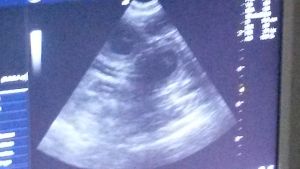

Röntgentermin beim Tierarztteam Jörn Emmerich in Vallendar 08. Januar 2014 Also ... gestern war es soweit und wir haben ein gaaaanz spezielles Bild von Keks geschossen. Zuerst war ich zwar etwas irritiert, dass das Bild mit Keks allein (ohne mich) gemacht wurde, aber der Maus ging es die ganze Zeit sehr gut und sie war auch ganz brav!!! Nach dem Bild durfte ich zur Besprechung rein. Herr Emmerich ist von Keks´ körperlichem und gesundheitlichen Zustand begeistert und er sieht keinerlei Probleme auf uns zukommen. Nichts desto trotz stehen er und Frau Dr. Häberlein nun auf Abruf bereit. ![]() Wer nun möchte, kann ja mal versuchen, die kleinen Kekskrümelchen zu zählen. Ich gebe einen Tipp: Es sind mehr als 6, aber weniger als 10. :-) Bisher ist Keks noch total entspannt, auch wenn wir am Samstag einen Fehlalarm hatten (Ihre Temperatur war schon auf 37,3 Grad). Nun wird fleißig jeden Tag Fieber gemessen und ein Protokoll geführt. Seit 2 Tagen schläft Keks in der "Keksdose" (davor in meinem Bett) und ich seit Samstag davor. Sie ist noch sehr ruhig, anhänglich und hat einen Bauch mit Beulenbildung :-) Die kleinen Kekskrümelchen kann sogar jetzt jeder sehen, der einfach Keks´Bäuchlein mal länger anschaut. Ich sage immer: Die Handballmannschaft übt das prellen :-) Da kommen auch die Gefühle der eigenen Schwangerschaft wieder hoch, wenn wir so zusammen liegen und die kleinen Krümelchen in meiner Hand sich drehen und wenden oder schon das Laufen üben ... einfach unbeschreiblich! Morgen kommen Babs, Rolf und Mini. Gästezimmer ist vorbereitet (seit Samstag :-)) und dann kann es bei Keks losgehen. Sobald wir Bilder und Info´s über die kleinen Kekskrümelchen haben, dann könnt Ihr das hier nachlesen - schneller über Facebook (wird öffentllich sein). Bis dahin bitte DAUMEN drücken! |